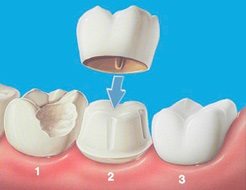

Protézielemével - Módszer protézis elhelyezést a pofák titán és a gyökér szerelhető a felületükön vagy szinterezett műanyag korona.

Kis hibák elülső fogak segítségével korrigálható héjak anyaga kerámia vagy porcelán. Megsemmisítése a hátsó fogak lehet korrigálni polimer vagy kerámia lapkák. Koronák használt részleges megsemmisítése a fogat, de a megőrzése a gyökér. Pótlása a veszteség egy vagy több foga esetleg egy híd protézis. De abban az esetben a teljes foghiány, akkor ajánlott használni protézielemével.